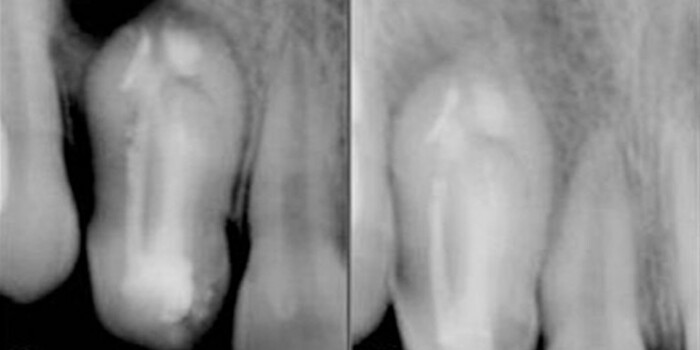

Инвагинация Зубов Или «Зуб В Зубе»

Инвагинация зубов (dens invaginatus), также известная как «зуб в зубе» (dens in dente), представляет собой редкую аномалию. Это состояние означает внедрение внешних твердых тканей зуба в пульпу. В этой статье обсуждается текущий протокол лечения инвагинации зуба у девочки 13 лет. Как и в большинстве...